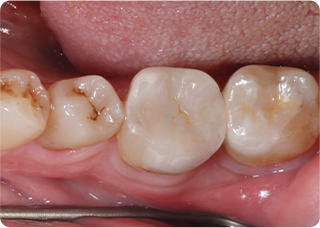

セラミックアンレー症例①

術前

むし歯除去

ラバーダム防湿

術後

| 主訴 | むし歯の治療をしたい |

|---|---|

| 治療期間/回数 | 2週間、2回 |

| 価格(税込) | 77,000円(税込) |

| リスク・副作用 | セラミックの破損、一時的な知覚過敏が生じる場合がある |

| ポイント | ラバーダム防湿をし、唾液や呼気の侵入を防ぎ湿度を下げることで、セラミックの接着力の向上を計った。接着力の向上により、脱離や破折の予防になる。 |